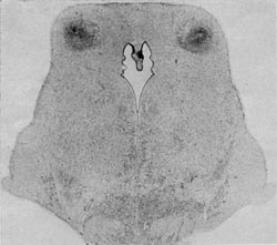

| conradsimon.org home (2000-2010) new decade IACC (invitation) Discussion points Figures/ tables: Blood flow >Ischemic injury Hemorrhagic injury Kernicterus Ski Injury Brain maturation Tables: Autism etiologies Birth asphyxia Brain maturation References: Autism etiologies Perinatal suboptimality 1-36 37-68 69-80 |